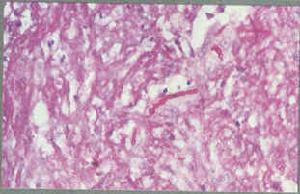

皮下組織暗色絲孢霉病暗色絲孢霉病暗色絲孢霉病是指由多種條件致病性棕色(暗色)真菌引起的皮下和深部組織感染。這種真菌不同於皮膚著色真菌病的病原菌,這些真菌的特徵性表現為在組織中形成有隔菌絲相,培養物中或多數病例組織中生長的真菌細胞壁中有色素形成。

與暗色絲孢霉病相對應,透明絲孢霉病是指組織內的真菌在普通HE染色時表現為透明、有分隔、分枝或不分枝,偶然可以呈念珠樣,但細胞壁不呈暗色。致病菌種類很多,如枝頂孢、鐮刀菌、帚霉、青黴、擬青黴和麴黴等。但過去已用致病菌命名的,如麴黴病、鐮刀菌病等則仍使用原名稱,如尚未確定菌種又符合上述定義者,可診斷為此病,這一名稱尚未得到廣泛接受。